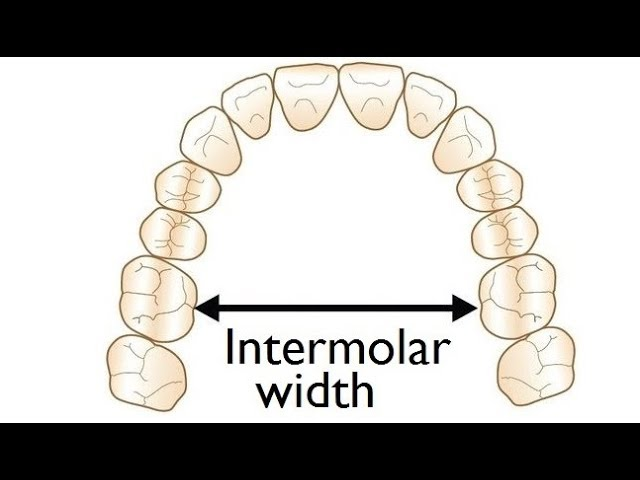

Guys , how do orthodontists actually check up if u have a narrow palate or not . Cuz Iam quite sure I have one . My paltal width is about 27 mm on a paper . Got actally diagnosed with it by an orthodontist how some how " hid it " without using an actuall paltal expander .

Like how do they even check ?